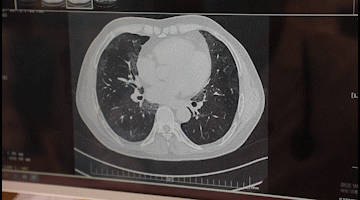

李先生入院后,胸科醫(yī)院吳昌歸院長、朱運奎副院長組織科室進行了深入討論,為其做了詳細檢查。醫(yī)生先做了導航下氣管鏡冰凍活檢,但病理未獲明確診斷。根據(jù)胸部CT特征、病變過程治療的反應,醫(yī)生懷疑是罕見的肺泡蛋白沉積癥。再經(jīng)肺泡灌洗液分析、PAS染色及診斷性分段灌洗后復查,證明醫(yī)生診斷正確。李先生確診為“肺泡蛋白沉積癥(繼發(fā)性)、肺炎、1型呼吸衰竭,并伴有慢性乙肝、高血脂癥等。

經(jīng)過4次的治療,李先生沉著于肺泡內(nèi)蛋白樣物質漸漸消失,灌洗液為透明色。復查胸部CT肺部病變明顯吸收。經(jīng)再次灌洗治療后病變完全吸收,恢復健康。